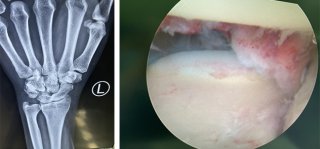

腕关节镜手术是一种用于诊断和微创治疗腕关节损伤与疾患的新技术,手术切口小而美观,除了可以避免常规切开手术在显露过程中对腕关节周围韧带/关节囊等组织造成的破坏,还可以避免传统切开手术留下明显手术疤痕的风险。而且,腕关节镜手术术后切口疼痛少,住院时间和术后固定,康复的时间往往都可缩短。此外,由于手术对关节囊和韧带的损伤与干扰小,术后形成的瘢痕粘连就小,从而有利于关节功能获得理想的康复。

腕关节镜下探究竟,月骨脱位不寻常

当我们摔倒时,如果手掌撑地,很容易造成腕关节损伤。人的手腕骨一共有8块,有舟骨,小多角骨,大多角骨,月骨,钩骨